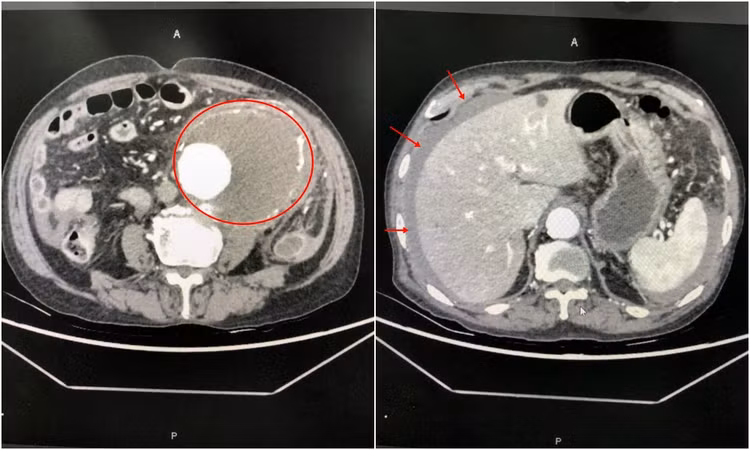

Kết quả chụp cắt lớp vi tính dựng hình mạch cho thấy khối phình động mạch chủ bụng có kích thước khoảng 10cm, có dịch máu trong ổ bụng và quanh khối phình. Các bác sĩ chẩn đoán người bệnh bị vỡ phình động mạch chủ bụng sau phúc mạc và chỉ định phẫu thuật khẩn cấp do sốc mất máu.

| Hình ảnh chụp cắt lớp khối phình động mạch chủ bụng và dịch máu tràn ổ bụng do vỡ túi phình - Ảnh BVCC |